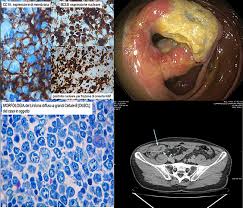

Colon cancer can be detected and prevented with a colonoscopy ballard said colonoscopies not only look for colon cancer, but they can prevent the vast majority of colon cancers by removing polyps. Apart from colon cancer, colonoscopy can be used to detect the following as well. Colorectal cancer is one of the most common cancers in both men and women nationwide. Colon cancer, however, starts inside of the bowel. Use of colorectal cancer screening tests.

Colon Cancer Screening Medlineplus Medical Encyclopedia from medlineplus.gov The decision to be screened after age 75 should be made on an individual basis. It can show large, more advanced cancers or masses.. Less often, part of the colon may need to be surgically removed to make the diagnosis. Apart from colon cancer, colonoscopy can be used to detect the following as well. Talk to your doctor about which test is right for you. It is used to determine if there are any polyps or growths in the tissue that line the inner surface. As mentioned, it is performed to identify the diseases lying underneath. If colon cancer develops, many treatments are available to help control it, including surgery, radiation therapy and drug treatments, such as chemotherapy, targeted therapy and immunotherapy.

Can a mammogram detect cancer. Colon cancer is sometimes called colorectal cancer, which is a term that combines colon cancer and rectal cancer, which begins in the rectum. Apart from colon cancer, colonoscopy can be used to detect the following as well. You might get radiation therapy if you have colon cancer and the tumor has attached to another organ in your belly, or if a tumor is found near the margins of the cancer that was removed. Cologuard is a noninvasive test. As mentioned, it is performed to identify the diseases lying underneath. Usually if a suspected colorectal cancer is found by any screening or diagnostic test, it is biopsied during a colonoscopy. Removing polyps during colonoscopy can not only prevent colorectal cancer, but also reduce deaths from the disease for years, according to a new study. A colonoscopy is a test that looks at the inner lining of the large intestine and rectum. It is used to determine if there are any polyps or growths in the tissue that line the inner surface. Patients whose colorectal cancer (crc) is detected during a screening colonoscopy are likely to survive longer than those who wait until they have symptoms before having the test, according to a. This represents an additional 3.5 million adults screened for colorectal cancer. As most colon cancer begins as precancerous polyps (called adenomas) detecting and removing these polyps are key to preventing cancer.

Capsule Endoscopy Versus Colonoscopy For The Detection Of Polyps And Cancer Nejm from www.nejm.org Colorectal cancer is one of the most common cancers in both men and women nationwide. We find polyps in at least 25 percent of men and women over the age of 50 through colonoscopies. Less often, part of the colon may need to be surgically removed to make the diagnosis. Usually if a suspected colorectal cancer is found by any screening or diagnostic test, it is biopsied during a colonoscopy. A colonoscopy is a test that looks at the inner lining of the large intestine and rectum. If you have had colon or rectal cancer, colonoscopy can also be used to look for new tumors. Patients at higher risk for colon cancer can begin screenings at even younger ages. No blood test can tell you if you have colon cancer.

It is considered a cancer screening process for early cancer detection. Colon cancer is one of the most preventable cancers, but it is often the most dangerous because there are no symptoms associated with it until it has progressed significantly. Use of colorectal cancer screening tests. About 140,000 people are diagnosed with colon cancer each year in the us and more than 50,000 people die of the disease annually. If colon cancer develops, many treatments are available to help control it, including surgery, radiation therapy and drug treatments, such as chemotherapy, targeted therapy and immunotherapy. A colonoscopy examines the lower half of the digestive system, mainly the large intestine. Can you detect ovarian cancer with colonoscopy and endoscopy. As mentioned, it is performed to identify the diseases lying underneath. A colonoscopy is performed by inserting a lighted, flexible tube called an endoscope into the rectum. Breast, colon or rectum, head and neck, liver and bile duct, lung, lymphoid leukemia. In the interim analysis, an earlier version of galleri accurately detected 29 cancers across 13 types: Colon cancer is sometimes called colorectal cancer, which is a term that combines colon cancer and rectal cancer, which begins in the rectum. Colon cancer can be detected and prevented with a colonoscopy ballard said colonoscopies not only look for colon cancer, but they can prevent the vast majority of colon cancers by removing polyps.